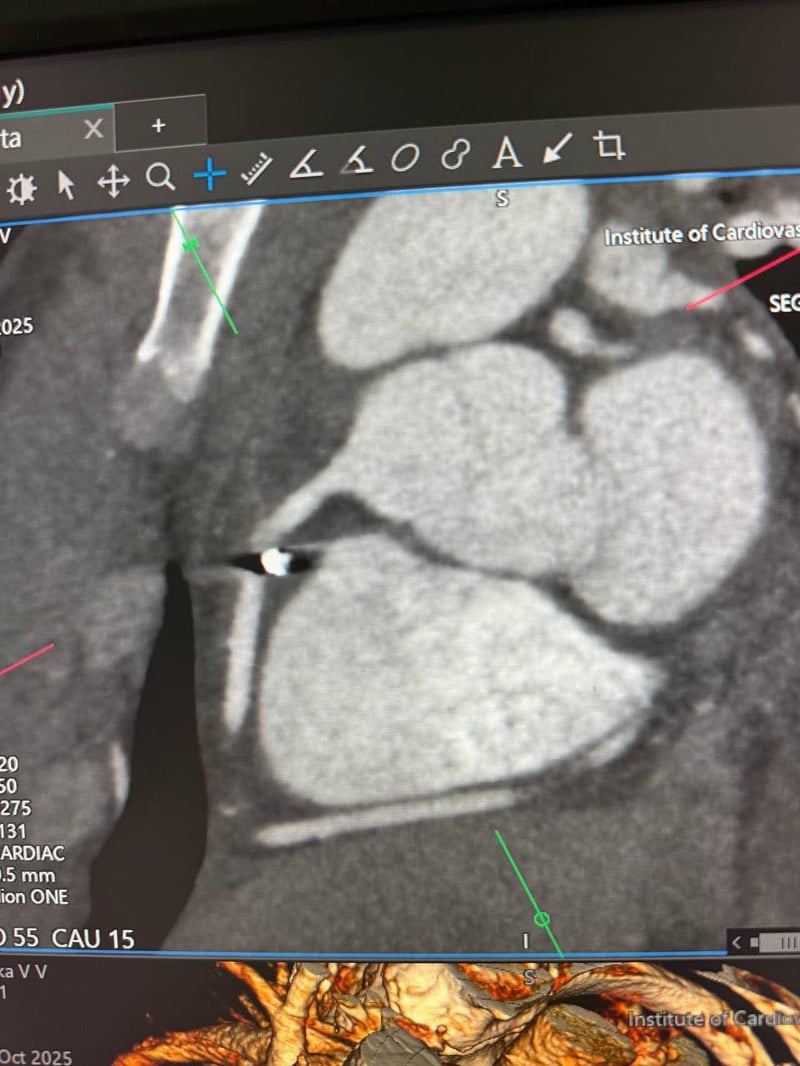

«Металевий уламок застряг у правій атріовентрикулярній борозні, біля правої коронарної артерії. Це надзвичайно небезпечна зона, де кожен рух може коштувати життя»,

— пояснили кардіохірурги.

Операцію успішно провів директор Інституту, академік Василь Лазоришинець разом із цілою командою фахівців. Уламок безпечно видалили, а серце Владислава тепер б’ється рівно.

Фото: Національний інститут серцево-судинної хірургії імені Амосова